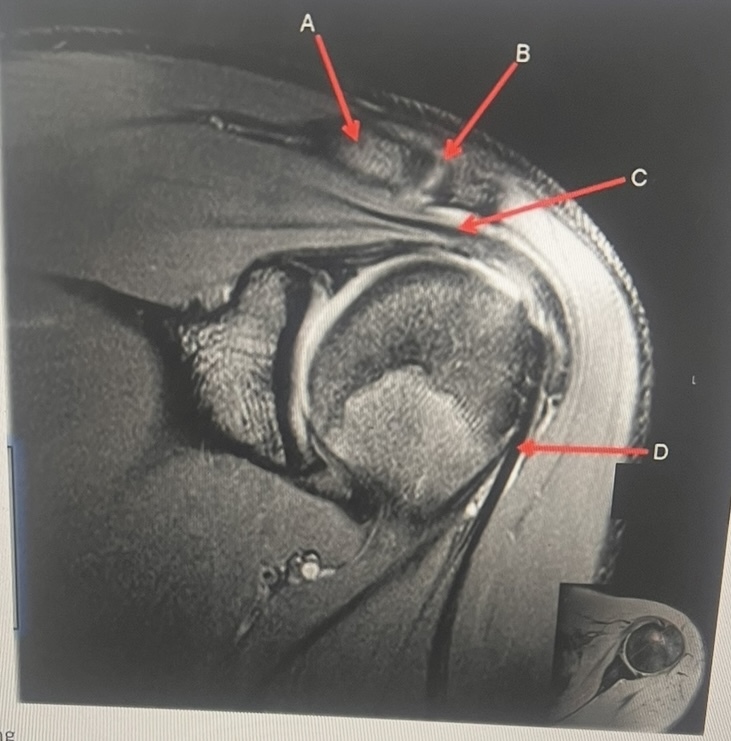

16

Q

MATCH to letters

1. Subscapularis muscle

2. Inferior labrum

3. Glenoid

4. Supraspinatus muscle

5. Clavicle

6. Superior labrum

A

18

clavicle, AC joint, supraspinatus tendon, biceps tendon

A. clavicle

B. AC joint

C. supraspinatus tendon

D. biceps tendon

20

B. superior labrum

C. supraspinatus muscle

D. glenoid

E. inferior labrum

F. subscapularis muscle